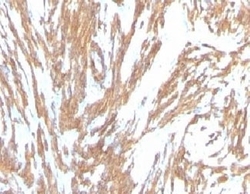

- Formalin-fixed, paraffin-embedded human Leiomyosarcoma stained with alpha Smooth Muscle Actin antibody (ACTA2/791). This image was taken for the unmodified form of this product. Other forms have not been tested.

- Formalin-fixed, paraffin-embedded human Leiomyosarcoma stained with alpha Smooth Muscle Actin antibody (ACTA2/791). This image was taken for the unmodified form of this product. Other forms have not been tested.